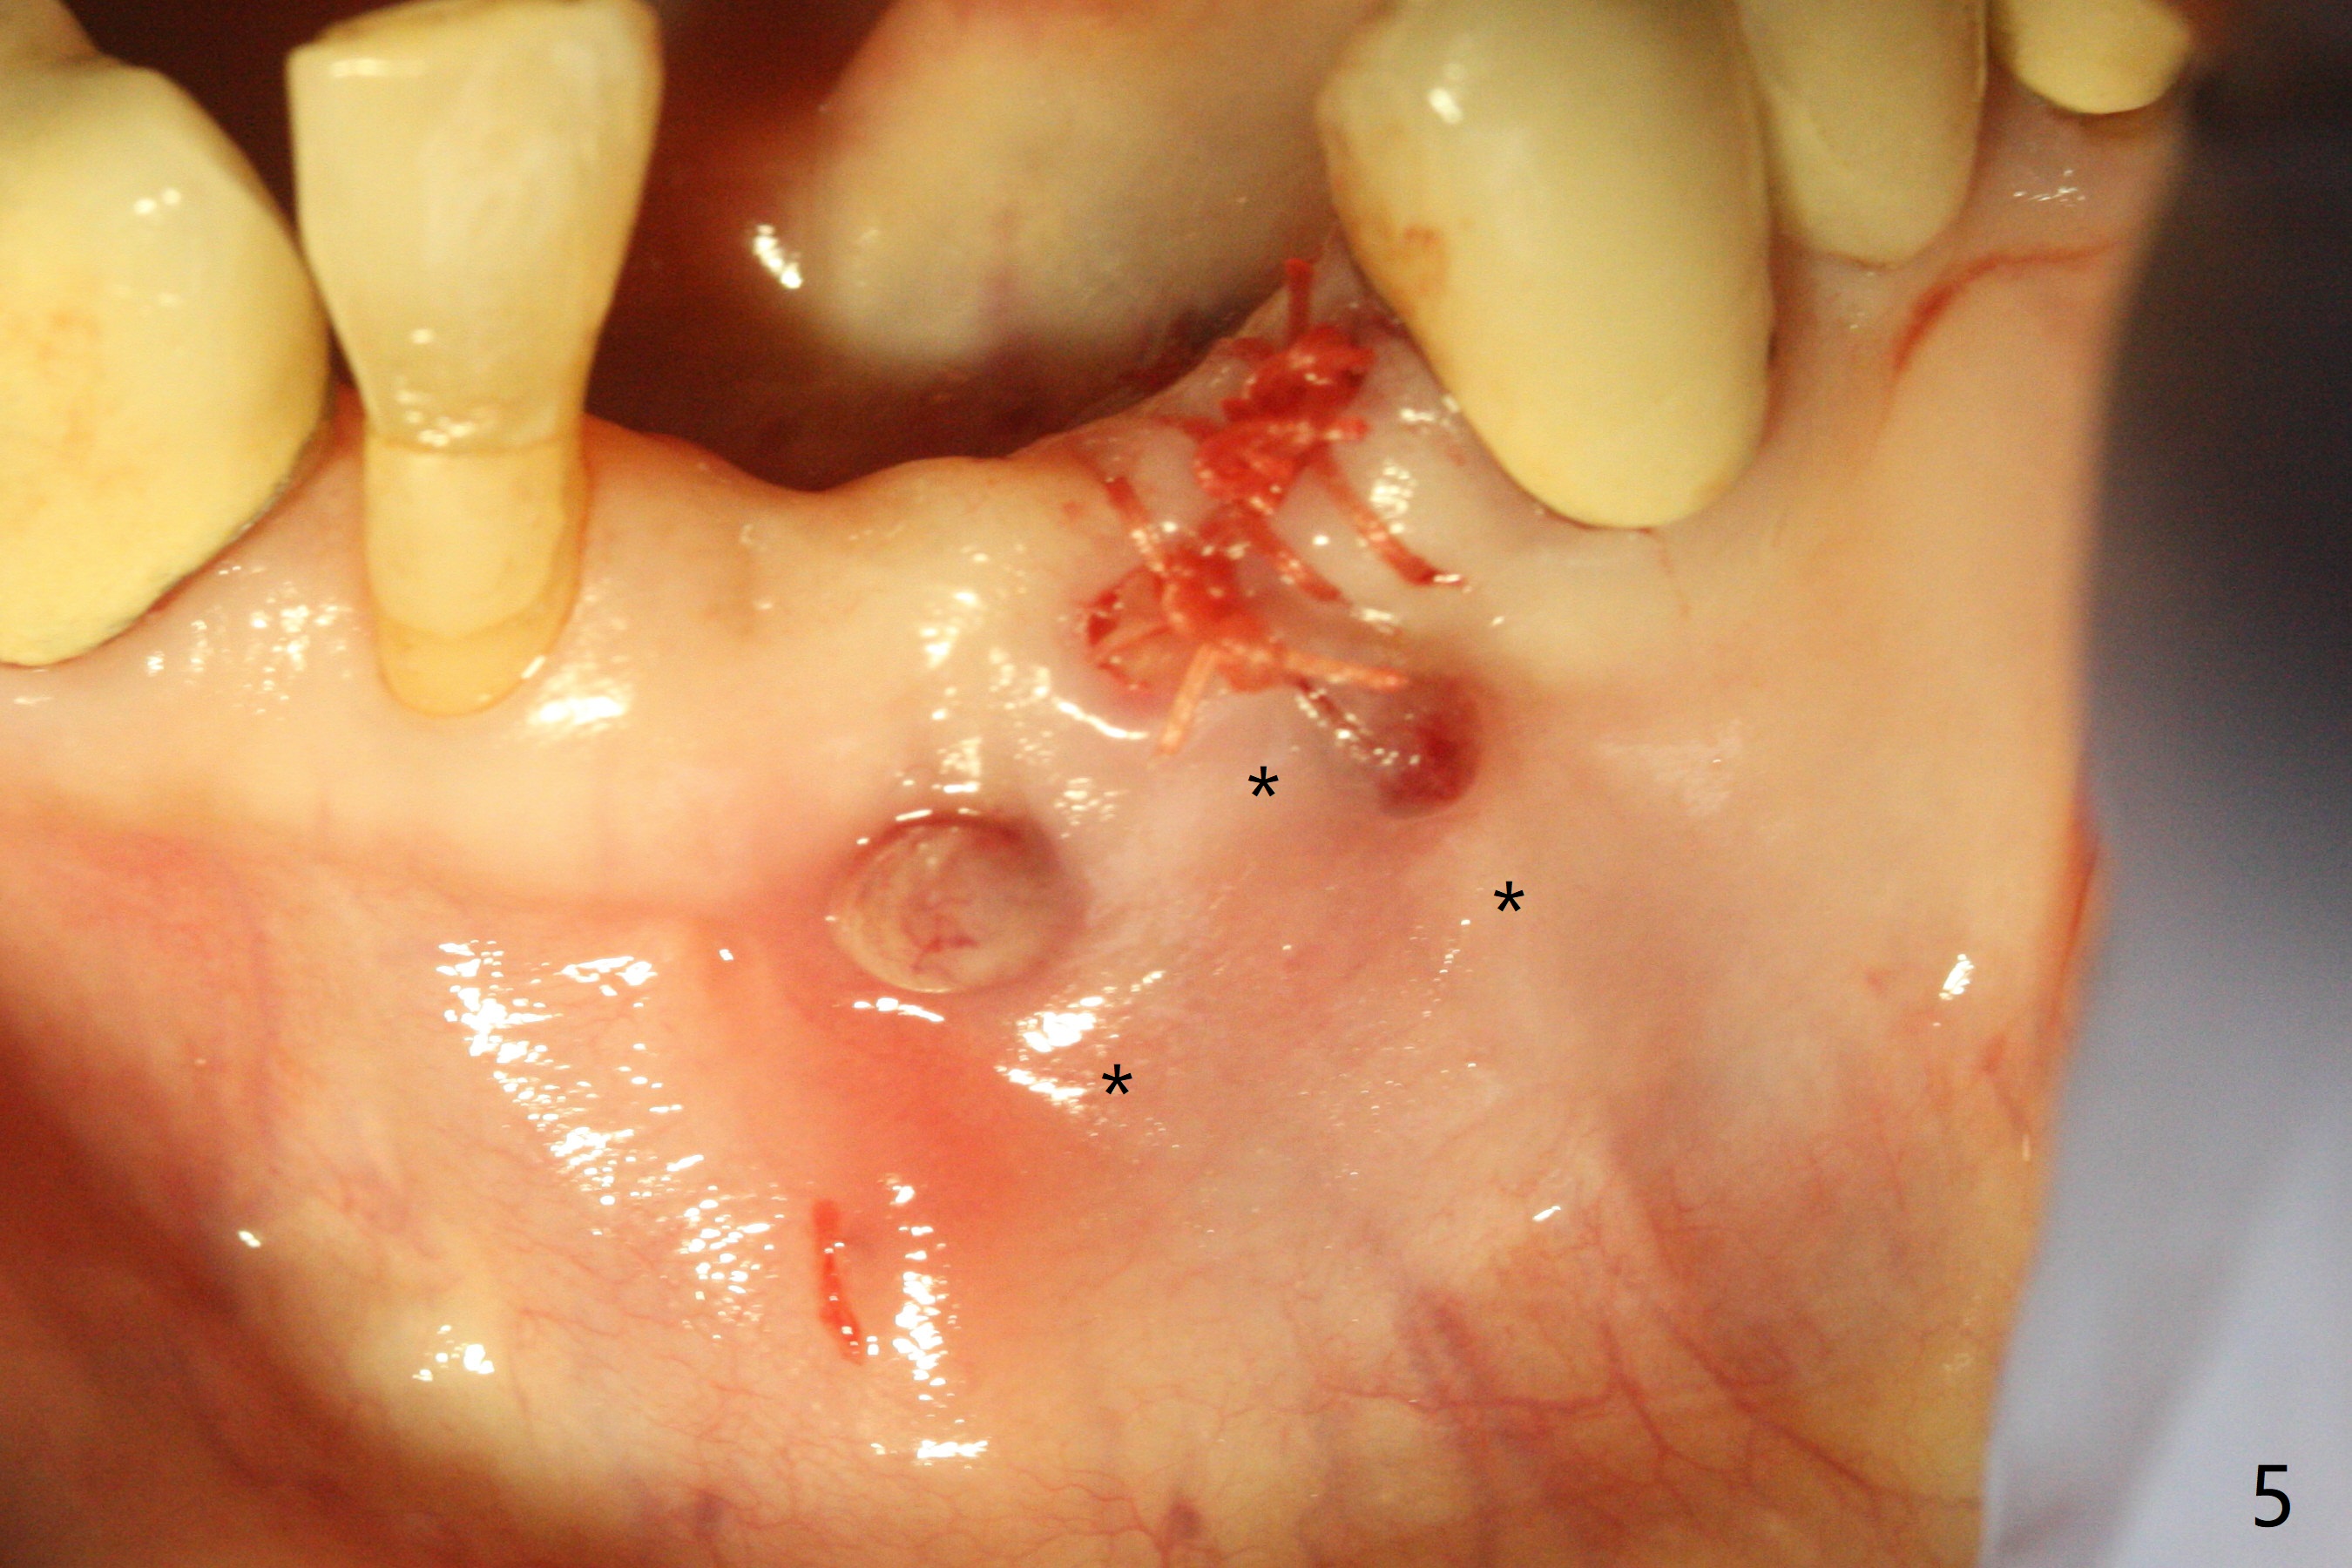

A 64-year-old woman requests extraction of the tooth #23 for lower partial (Fig.1). Since there are 2 buccal sinus tracks, another residual root is suspected (?). After shown loss of the buccal plate (Fig.2,3), the patient agrees to have socket preservation with allograft (Fig.5,6 *) and BioXclude (Fig.4 >). The suspected residual root is not explored considering the 2 sinus tracks being associated with the lesion of #23 (Fig.2,3). Cytoplast is not used because of time constraint and fear of gingival dehiscence associated with extensive dissection. In fact the sinus tracks shrink in a week, while the buccal plate remains bulging (Fig.7 *) and the socket heals (Fig.8 >). The buccal plate is flat (no swelling) 1 month postop (Fig.9).